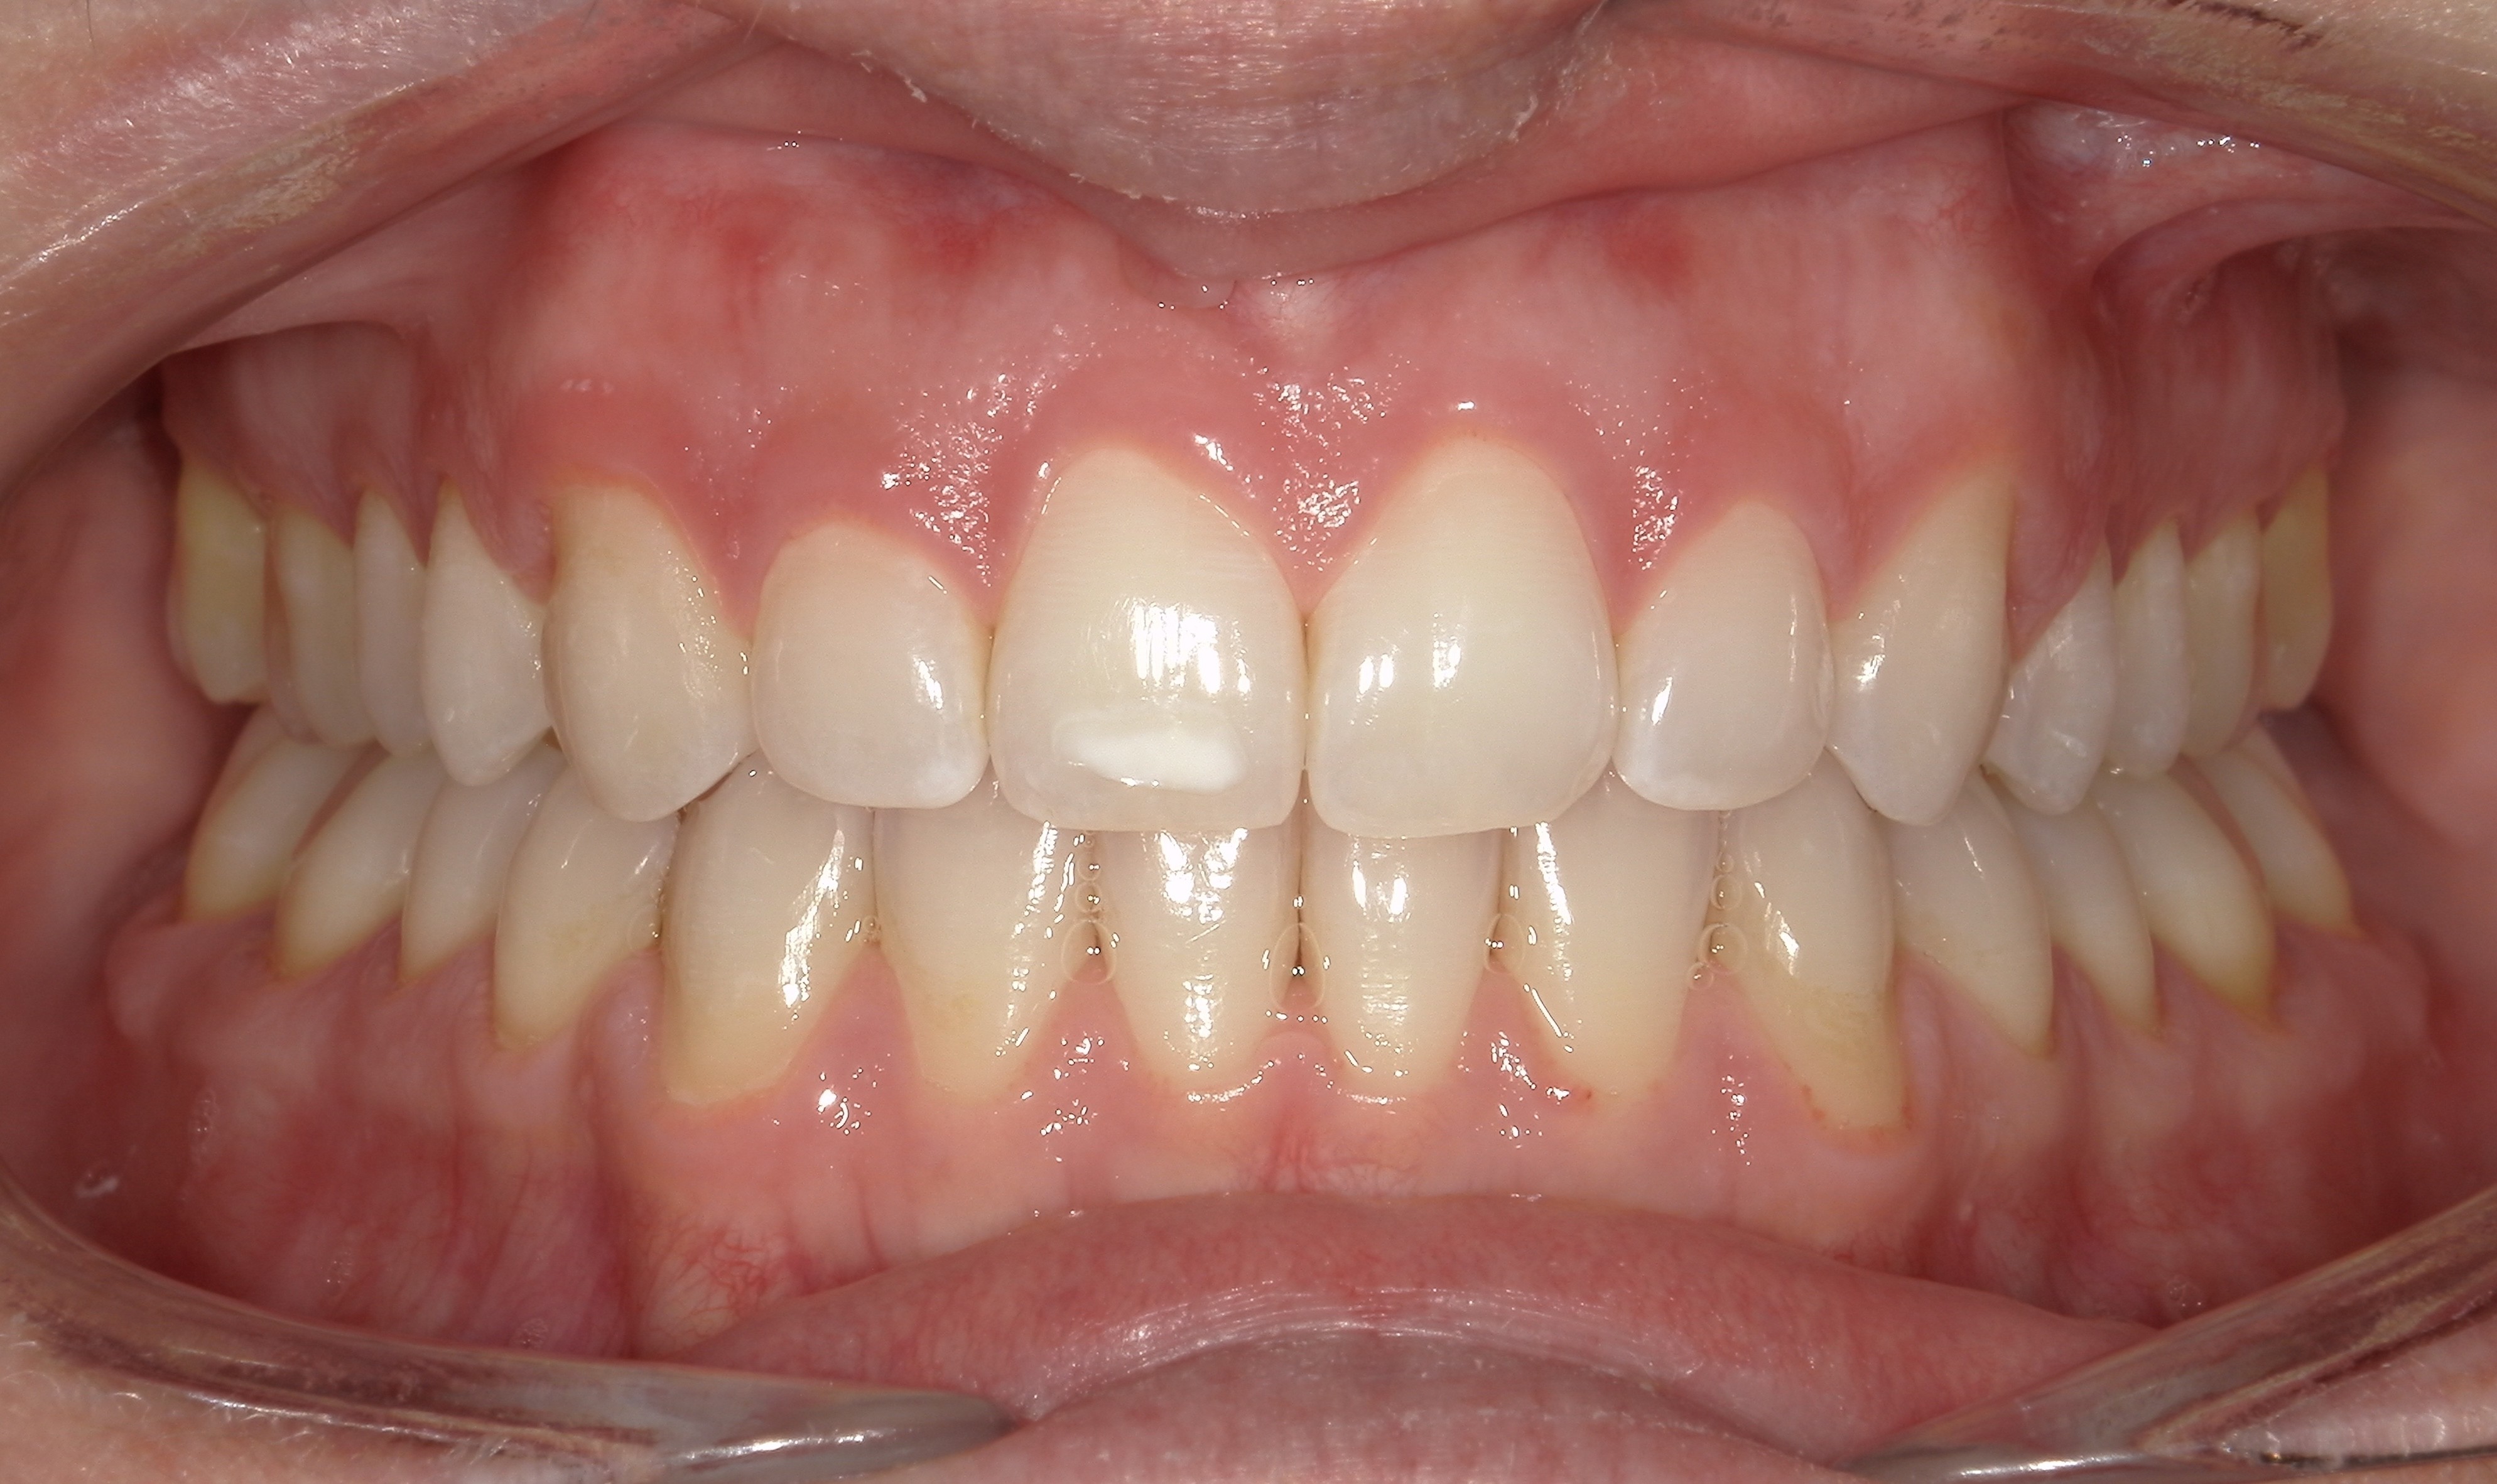

Initial treatment

INTRAORAL

Diganosis: Moderate lower anterior crowding, square and narrow maxilla, rotated #19

Adjuncts: Attachments